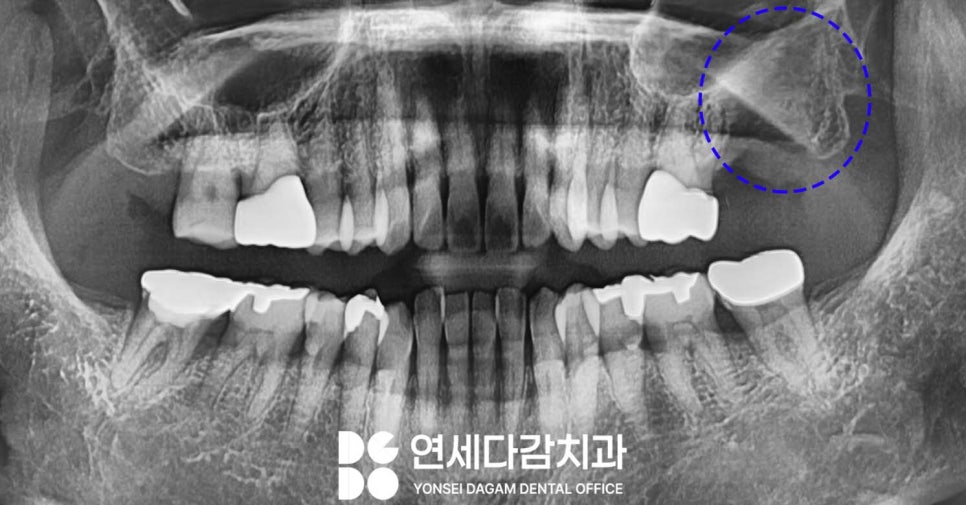

송파역 치과 에서 분석해 봤을 때

어금니의 병소가 커지면서,

주변 구조에 변화를 일으켜

발육 위치가 변이된 것으로 판단됩니다.

간혹 이런 일이 있을 수 있습니다.

구강 내 병소가 커지면서

주변 조직과 구조물에

압력을 가하거나, 주변 골조직을 파괴하여

이로 인해 매복된

사랑니의 발육 방향과 위치가

변할 수 있기 때문입니다.